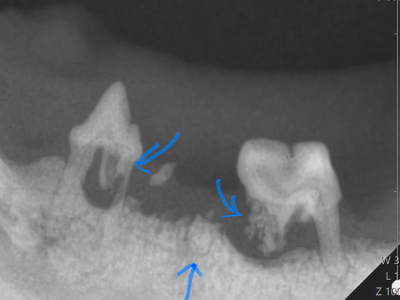

症例(猫1)X線

X線で確認すると両隣の歯も溶けてきています。

痛みの原因になるので全部抜歯となりました。 -